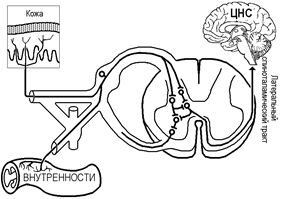

С тех же позиций можно объяснить фантомные боли при ампутации конечностей (рис.): желатинозная субстанция не имея не имея влияний со стороны неноцицептивных афферентов удаленной конечности не тормозит ноцицептивные афференты других областей тела и нейрон Т пропускает ноцицептивные импульсы к высшим отделам, которые воспринимаются как импульсы с удаленных конечностей (как отраженные боли, отраженные сознанием на удаленную конечность[Б18]).

Рис.. Объяснение фантомной боли по теории воротного контроля.

Вторая причина-ветвление первичных ноцицептивных афферентов в спинальных нервах с образованием двух или более коллатералей, так что одно волокно иннервирует и поверхностную, и внутреннюю структуры (рис.).

Рис.. Пути возникновения отраженной боли. В некоторых случаях ветви одного и того же ноцицептивного афферента иннервируют и поверхностную, и глубокую ткани.

Аксон-рефлекс (axon-reflexus) — общее название рефлексов, осуществляющихся по разветвлениям аксона без участия тела нейрона: рефлекторная дуга аксон-рефлекса не содержит синапов и тел нейронов, возбуждение идет афферентно, но одной ветви аксона, затем передается нa другую ветвь и эфферентно распространяется к эффекторному органу. С помощью аксон-рефлекса может происходить регуляция внутренних opгaнов и сосудов и болевой чувствительности в определенной степени независимо от ЦНС.

| Рис.. Схема аксон-рефлекса. |